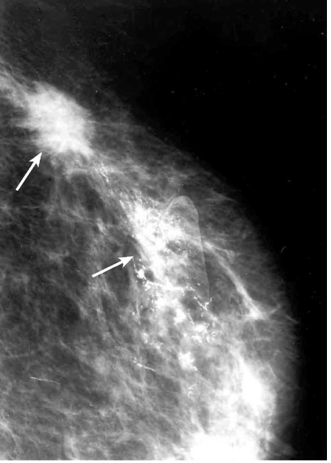

הבדיקה החשובה ביותר לגילוי מוקדם של שאתות השד היא הממוגרפיה. בבדיקה זו ניתן להדגים את רקמת השד, סמיכות הרקמה, הסתיידויות, עובי העור, צורתו וצל כלי הדם. צל בעל סמיכות יתר המכיל בתוכו מיקרוקלסיפיקציות במספר רב, בעל גבולות בלתי סדירים, כמו קרניים, עם זנב של רקמה סמיכה היוצאת ממנו, ריבוי והדגשה של כלי הדם או התעבות העור ושקיעת הפטמה, כולם מהווים סימנים מחשידים לקיום שאת ממארת בשד (תצלומים 22.12, 23.12). בהגדלה ניתן לראות את הסימנים לממאירות בצורה ברורה יותר (תצלום 24.12).

הסיבות אשר בעטיין נגע מסוים איננו ניתן למישוש הן: שאת קטנה, שאת המתבטאת רק בהסתיידויות זעירות ללא גוש (תצלום 25.12), שד גדול או מגורגר המקשה על הבדיקה הקלינית. הממוגרפיה, למרות יכולתה לגלות נגעים בלתי ניתנים למישוש, איננה בדיקה חד-משמעית וסגוליותה נמוכה. מחד גיסא, גוש סמיך בעל שוליים בלתי סדירים, עם הקרנת קוריות לסביבה מעיד בביטחון על תהליך ממאיר. מאידך גיסא, הסתיידויות גסות, הסתיידויות כיסתיות או הסתיידויות פסיות סדירות וכן נגעים בעלי סמיכות דומה לזו של שומן, מצביעים על תהליך שפיר.

מצויה שורה של ממצאים רנטגניים הנוגעים לפי הספרות לקבוצה שבה קיימת חפיפה בין סימני ממאירות לבין סימני שפירות. אלה כוללים: הסתיידויות זעירות, בלתי סדירות, המסודרות בקבוצות, או שמספרן הוא גדול מ-20, גוש שאיננו מוגדר דיו, שינוי מקומי במהלך קוריות השד, א-סימטריה בהופעת רקמת השד וממצא שנתגלה בין ביצוע ממוגרפיה אחת לזו שאחריה.